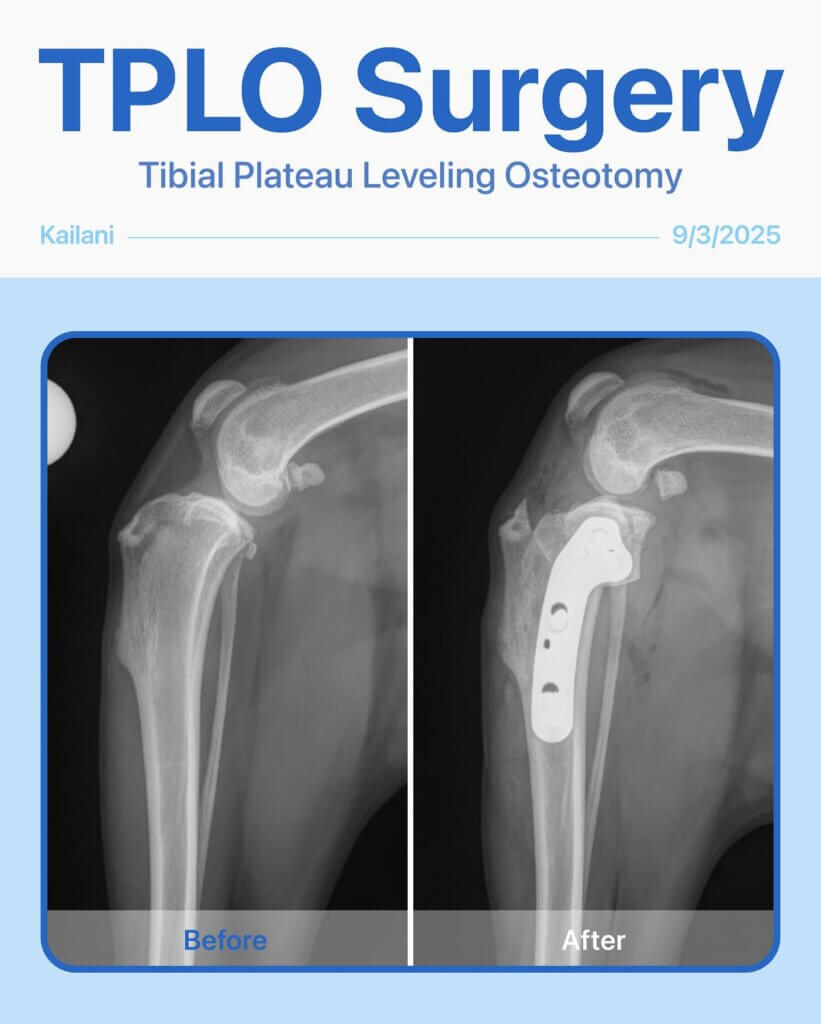

Meet Kailani, a 1-year-old Poodle mix who had been limping on her left back leg for the past 4 months. After a thorough exam and radiographs, we found she had a cranial cruciate ligament tear—a common injury that can make every step painful.

She needed TPLO surgery to restore stability and get back to her playful, happy self. Since both legs were affected, we decided to start with the left first to give her the best chance at a smooth recovery.